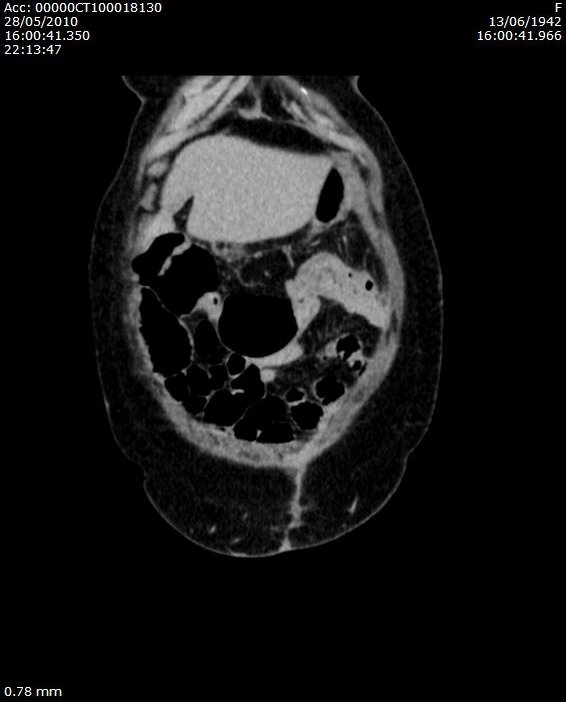

a colon transversum felétől diffúzan vastag a bélfal, submucosa echoszegény, spasticus a bél, haustratio eltűnt, paracolicus zsír beszűrt, kis folyadék az elülső pararenalis tér mélyén